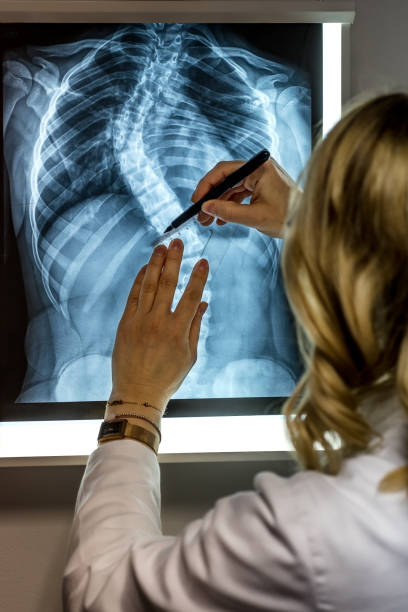

전문의사가 알려주는 증상을 통해서 확인을 해보시는게 가장 정확합니다.

약 7분 정도의 영상입니다. 꼭 시청하시고 올바른 척추측만증 증상을 확인해보세요.

척추측만증의 초기 증상은 무엇인가요?

척추측만증의 초기 증상은 어깨 높이의 차이, 등과 어깨가 비대칭하게 보이는 것, 옆구리의 곡선이 비정상적인 형태로 나타나는 것 등이 있을 수 있습니다. 또한 어린 아이들의 경우, 차렷 자세에서 허리를 구부리게 하면 등높이의 차이가 눈에 띄는 경우도 있습니다. 이러한 증상이 있을 경우 의사를 찾아가서 진단을 받는 것이 중요합니다.